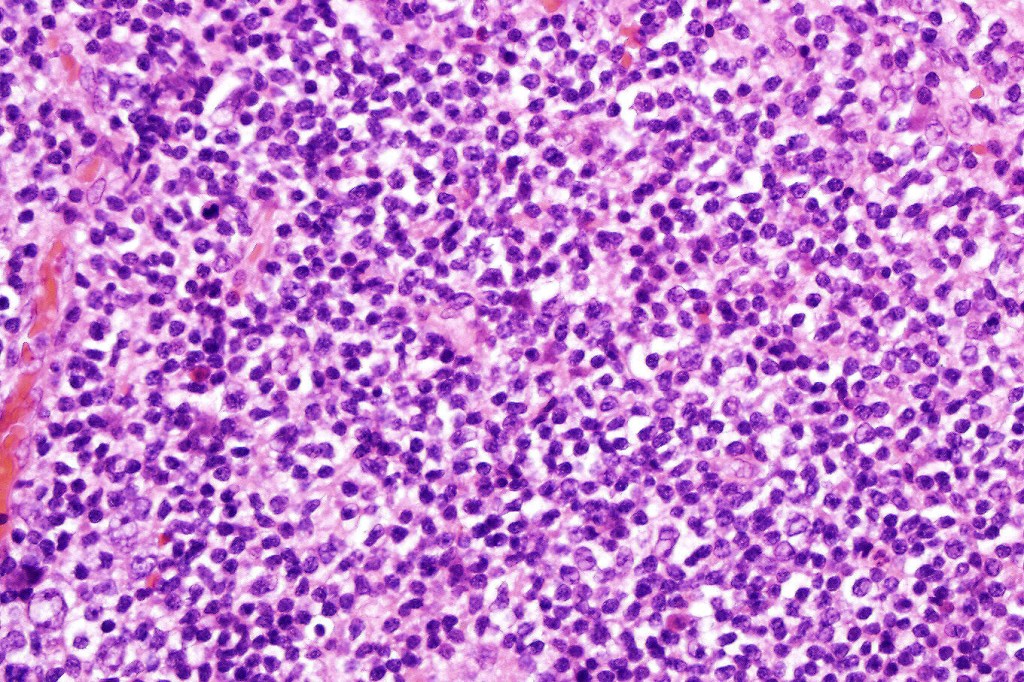

Histological features

•Follicular infiltration by atypical lymphocytes & Sézary cells

•Eosinophils sometimes conspicuous (eosinophilic folliculitis-like appearance)

•Large cell transformation occasionally present